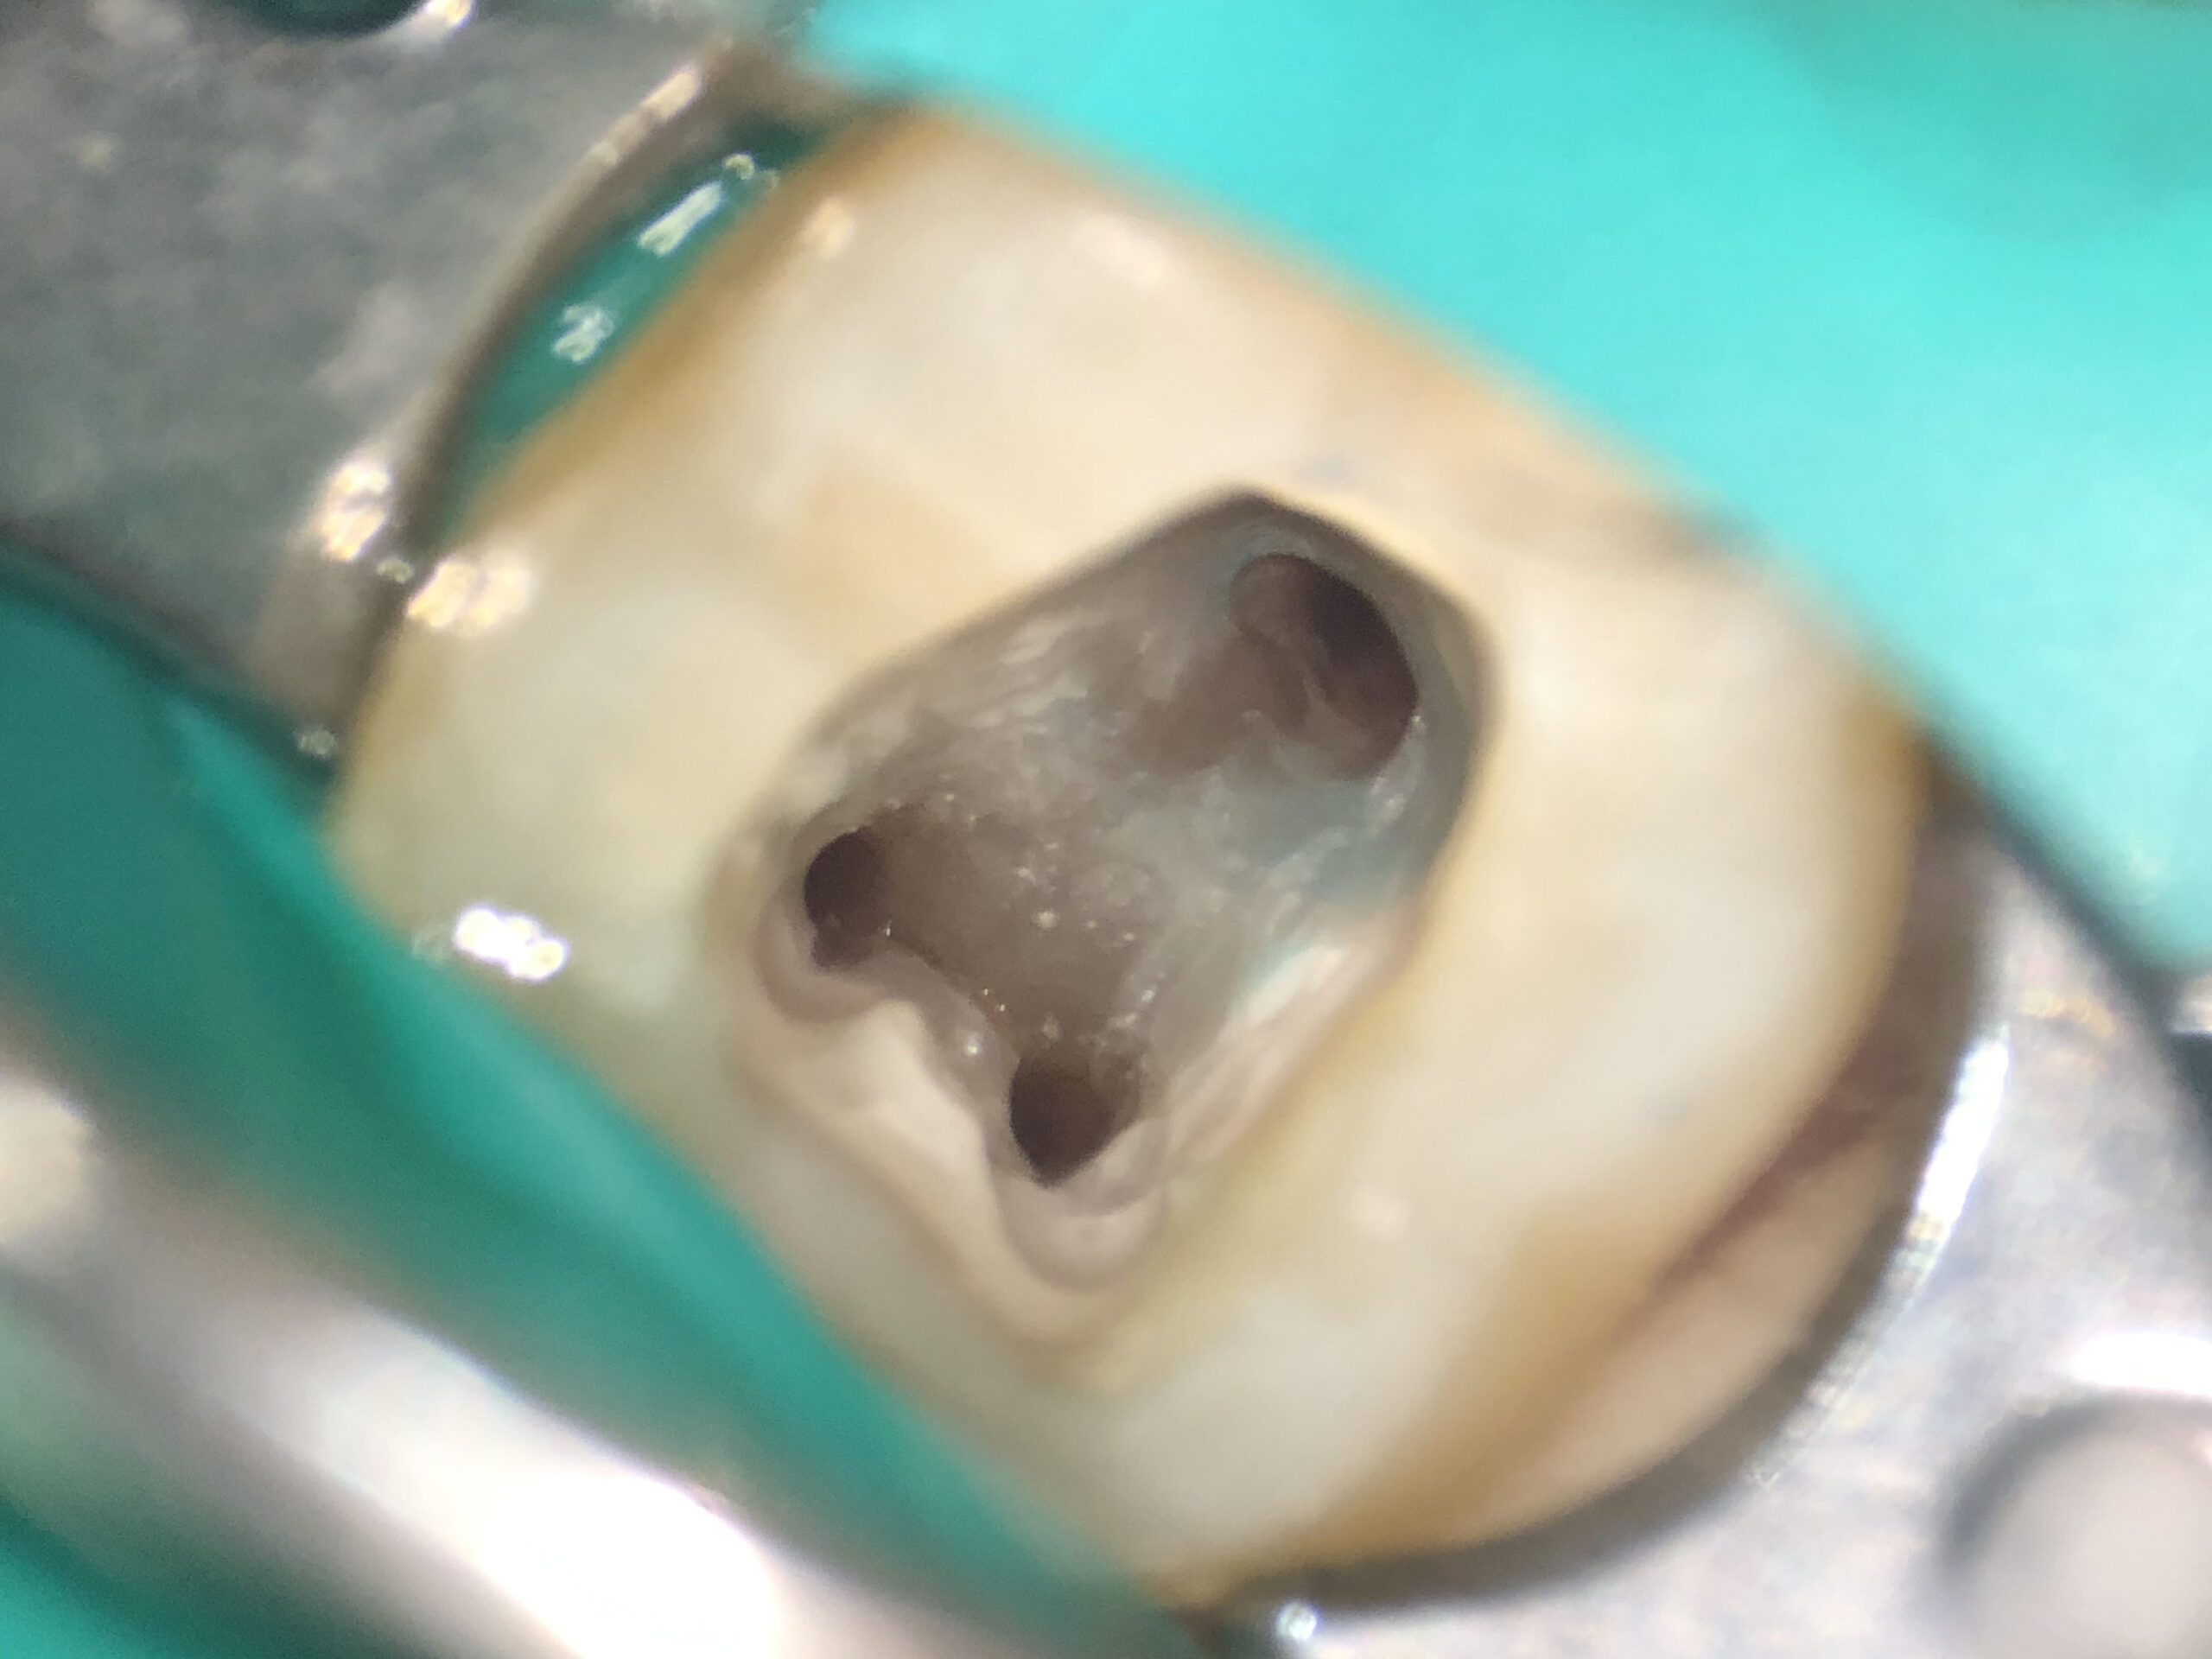

こちらが根の中の神経を綺麗に取り除き、消毒した後の状態をマイクロスコープで見た写真になります。

古い詰め物を除去したところ、詰め物の下に茶色く虫歯に感染してしまった歯質が認められました。虫歯を染める液体や顕微鏡を用いて徹底的に虫歯を取り除きます。ここで虫歯を取り残してしまうと、細菌が根の中に再感染してしまう可能性があります。そのため、今後の再発を防ぐためにはしっかり時間をかけて虫歯を取り切ることが非常に重要です。